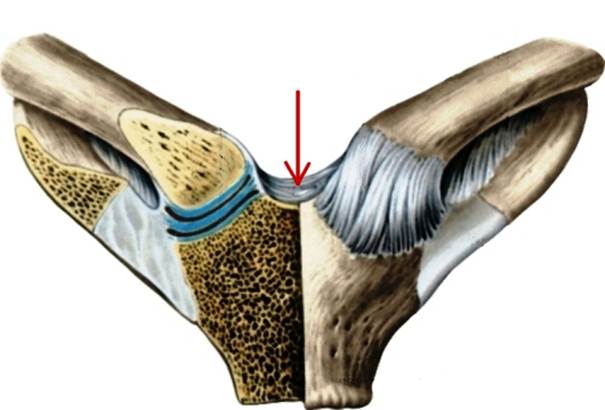

S: Стрелка указывает на art. Costotransversaria

S: Стрелка указывает на art. Capitis costae

S: Стрелками выделен art…